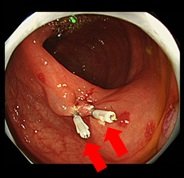

- 大腸内視鏡検査

| 大腸の病変の有無を調べる検査です。本検査では大腸ポリープの有無や経過観察、大腸粘膜の炎症等の診断などを目的としています。本検査でも、病変の状態によってはその場で治療を行うことがあります。 | ||||

|||

| 大腸ポリープ | 削除+止血クリップ | |||